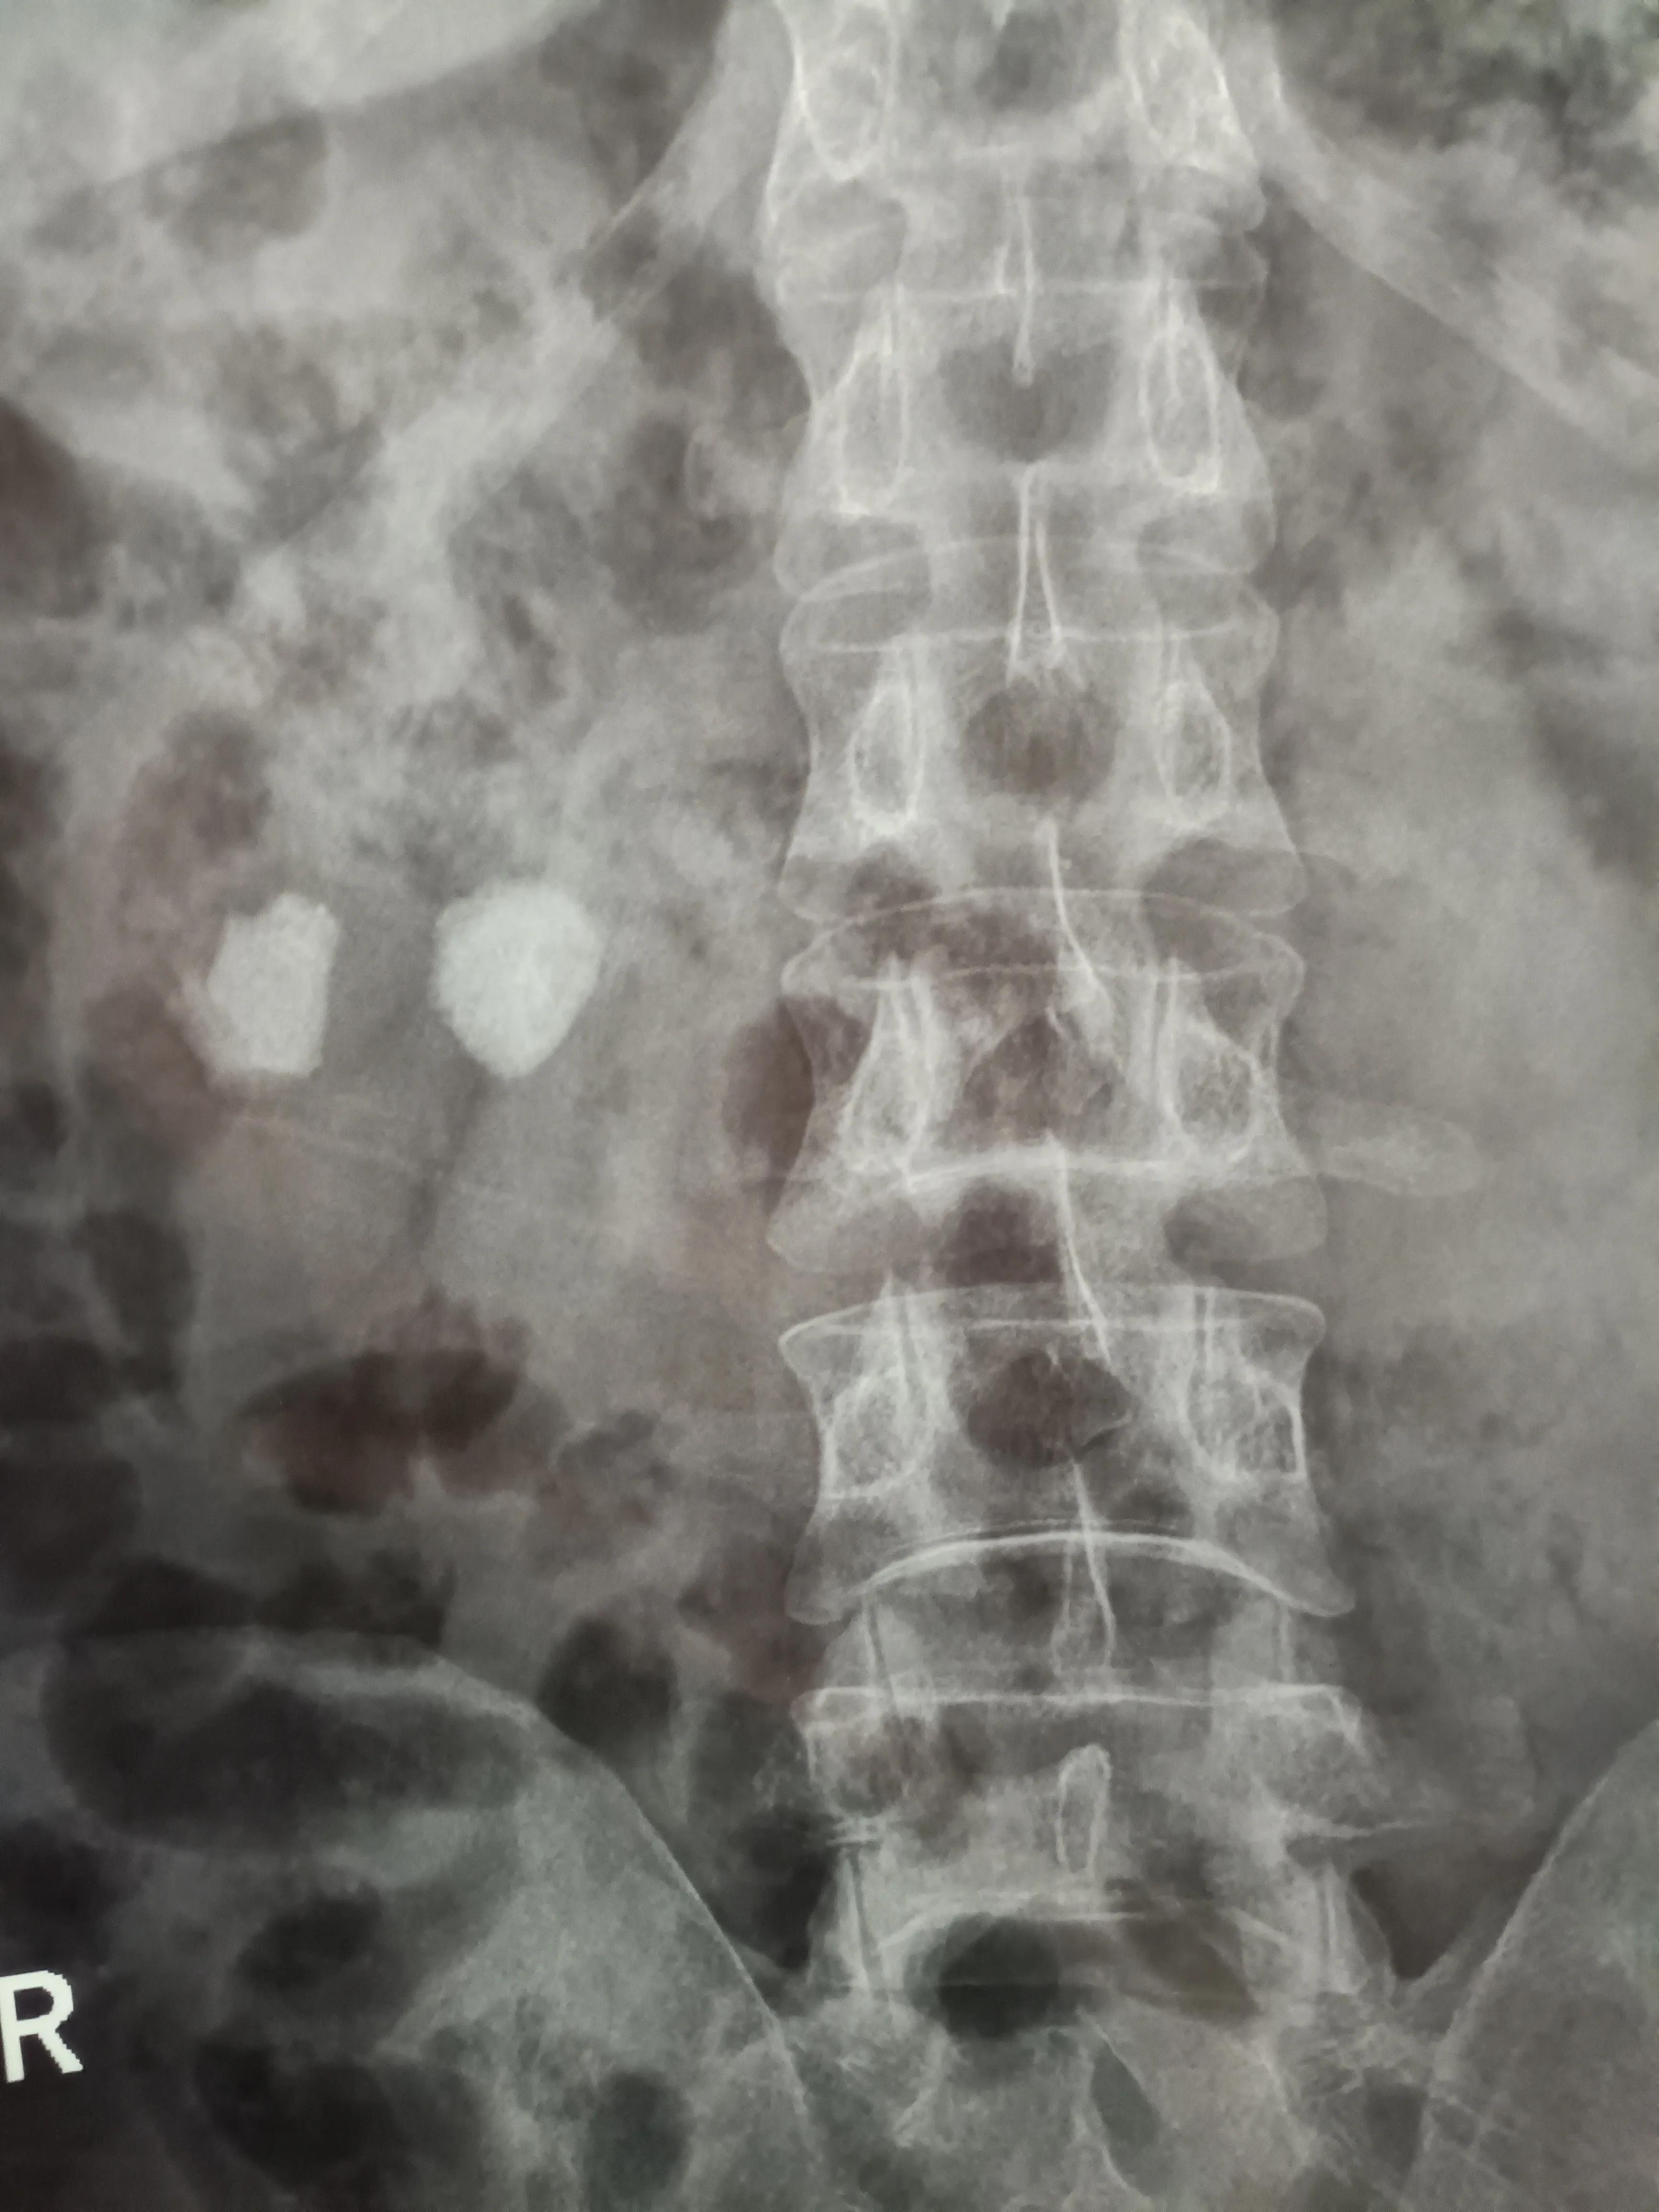

两颗大石头清晰可见